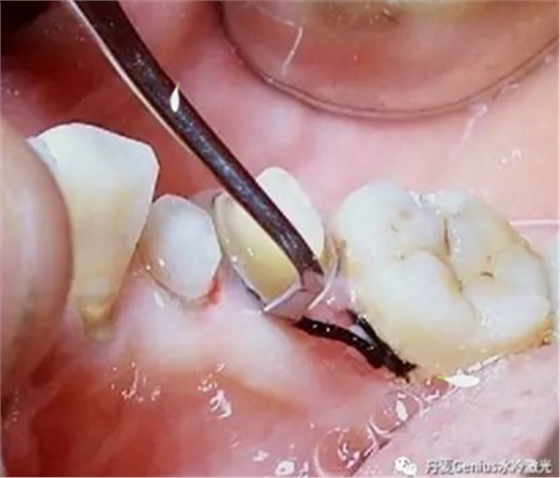

排齦-排齦操作前3分鐘,表麻涂抹于牙齦上,有效緩解剝離游離齦過(guò)程中產(chǎn)生的疼痛